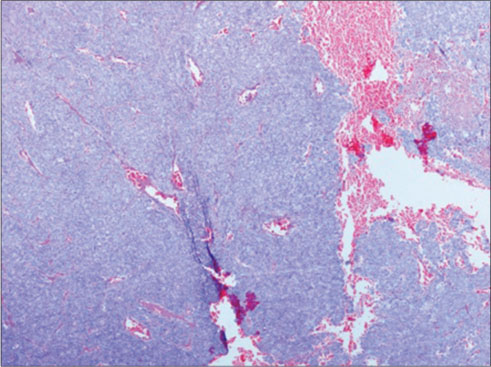

A 56-year-old gentleman presented with painless progressive swelling on the left side of the abdomen for 6 months, associated with skin ulceration and discharge without any constitutional symptoms. Contrast-enhanced computed tomography (CECT) of the abdomen showed 166 mm × 123 mm × 45 mm heterogeneously enhancing anterior abdominal mass in the left lumbar region, with loss of fat plane between the mass and underlying muscle. The lesion was extending up to the skin with focal areas of ulceration, without intraperitoneal or retroperitoneal extension. CECT of the chest revealed well-defined heterogeneously enhancing lesions in the left lower lobe suggestive of metastases. Biopsy from the primary lesion showed medium-sized neoplastic cells arranged in sheets [Figure 1] with scanty cytoplasm [Figure 2] and round-to-oval nuclei with inconspicuous nucleoli consistent with poorly differentiated malignancy. Immunohistochemistry (IHC) showed leukocyte common antigen-negative, Melan A-negative, pancytokeratin dot-like positive [Figure 3], CD34-negative, cytokeratin 20 (CK20) dot-like positivity [Figure 4], CD 56-positive, CD 117-negative, and chromogranin-negative. Morphology with IHC correlation was suggestive of MCC. Brain and bone scans were normal.

| Figure 1: Cellular lesion arranged predominantly in sheets, (H and E, ×40)